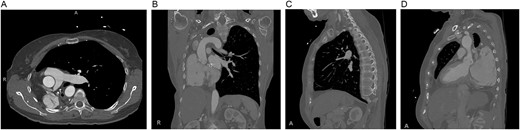

Preoperative computed tomography of the chest. Axial (A), coronal (B) and sagittal (C, D) views demonstrating displacement of the heart and left lung into the right hemithorax.

Most open cardiac operations after pneumonectomy are coronary artery bypass grafts with few valve replacements [2]. Prior pneumonectomy poses certain uncommon technical challenges related to exposure for both the valve(s) of interest and cannulation strategy for CPB. This case was challenging given the significant mediastinal shift to the right. Neither median sternotomy nor anterolateral thoracotomy was appropriate due to the displacement of the heart and left lung. The RV abutted the right chest wall with the right atrium in the posterior right pleural space. A posterolateral thoracotomy was necessary to access the tricuspid valve. Additionally, the aorta and IVC were initially inaccessible for cannulation, so the femoral vessels were used, with an additional SVC cannula once it was exposed.